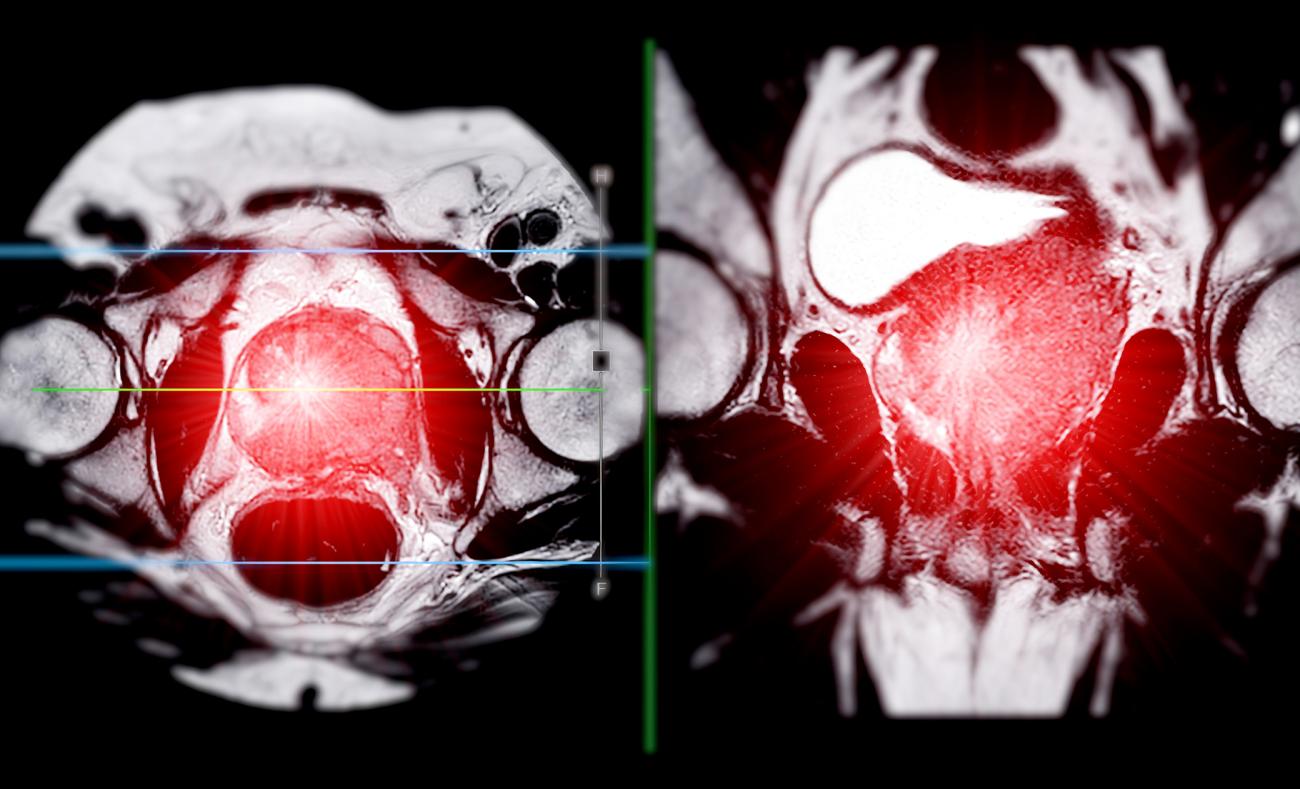

To explain the paradox of elevated levels of the androgen-reducing UGT2B17 in metastatic prostate cancer, Dong and his team’s analysis targeted the enzyme, which is a type of protein, using mass spectrometry-based proteomics. Mass spectrometry is a specialized approach to determine the weight of molecules in a sample, with proteomics geared specifically toward profiling proteins, their interactions and modifications, and how they affect cell function in the body.

Dong’s analysis of UGT2B17 — which included large, multi-institutional Canadian cohorts — focused on characterizing other mechanisms that the enzyme performed in the body other than eradicating androgen hormones, which is UGT2B17’s enzymatic activity. The team’s investigation resulted in the discovery of significant interactions between UGT2B17 and two other cancer-associated oncogene proteins: protein disulfide isomerase (PDI) and Src kinase.